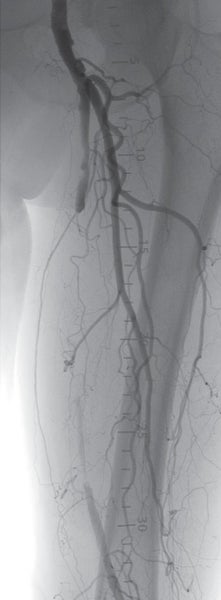

対側CFAより6 Fr 45 cm長のガイディングシースを挿入し山越えにて左EIA遠位部に進めた。この時点で圧波形は問題なかったため、手技を継続することとした。まず、5.5 Fr 100 cm長のガイディングカテーテルのバックアップ下、IVUSガイドに0.014 inchガイドワイヤー(先端荷重3 gポリマージャケットタイプ)を進めたところ、比較的容易にガイドワイヤー通過に成功した。IVUSでは全長にわたり intraplaqueを通過していたものの、血栓成分の多いプラークと考えられた。このため、5.5 FrのガイディングカテーテルをSFA遠位部に先進し、フィルターワイヤー(径 8 mm)を膝窩動脈に留置し遠位部保護を行った。続いて、5.5 Frガイディングカテーテルを用いて血栓吸引を行ったうえで、小径バルーン径 4.0 mm / 長 220 mmを使用し6 atmで前拡張した。(図3)この時点で造影にて末梢塞栓のないことを確認しフィルターワイヤーを回収、0.035 inchガイドワイヤーを用いて7 Fr 55 cm長のガイディングシースへ交換した。0.014 inchガイドワイヤー(先端荷重 1 g 親水性コートタイプ)を挿入後、SFA遠位よりバイアバーン® ステントグラフト径 7.0 mm / 長 150 mmを留置し、バルーン径 6.0 mm / 長 80 mmを用いてステントグラフト内のみ 18 atmで後拡張を行った。続いて、SFA近位部のlanding zoneをIVUSマーキングしたうえで、(図4)バイアバーン® ステントグラフト径 7.0 mm / 長 100 mmを追加留置した。先述のバルーン径 6.0 mm / 長 80 mmを用いて高圧拡張の後、近位部のみバルーン径 7.0 mm / 長 100 mmを使用し12 atmで後拡張を追加した。IVUSにてステントグラフトの拡張が良好かつmalpositionがないことを確認した。 最後に、EIAに対してベアメタルステント(BMS)径 10 mm / 長 60 mmを留置、後拡張を行って手技を終了した。(図5、6)